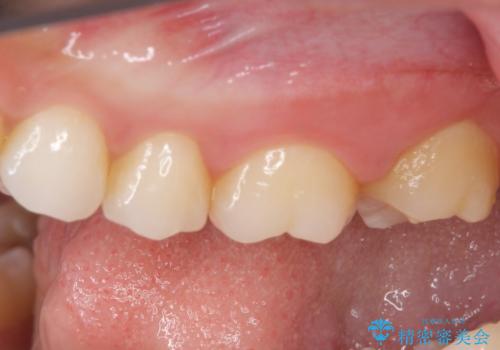

ゴールドインレーは銀歯のインレーやセラミックインレーと比べ、「技工操作の精度が高く、適合が著しく良い」というメリットがあります。特に上の奥歯は歯科医師の操作が行いにくいため、「適合の良さ」は再治療のリスクを防ぐ上でとても重要な要素となります。

上の奥歯は金属色が見えることもないため、審美的な問題は全くありません。

咬み心地はとても良好で、全く違和感がなく、患者様には大変満足していただきました。